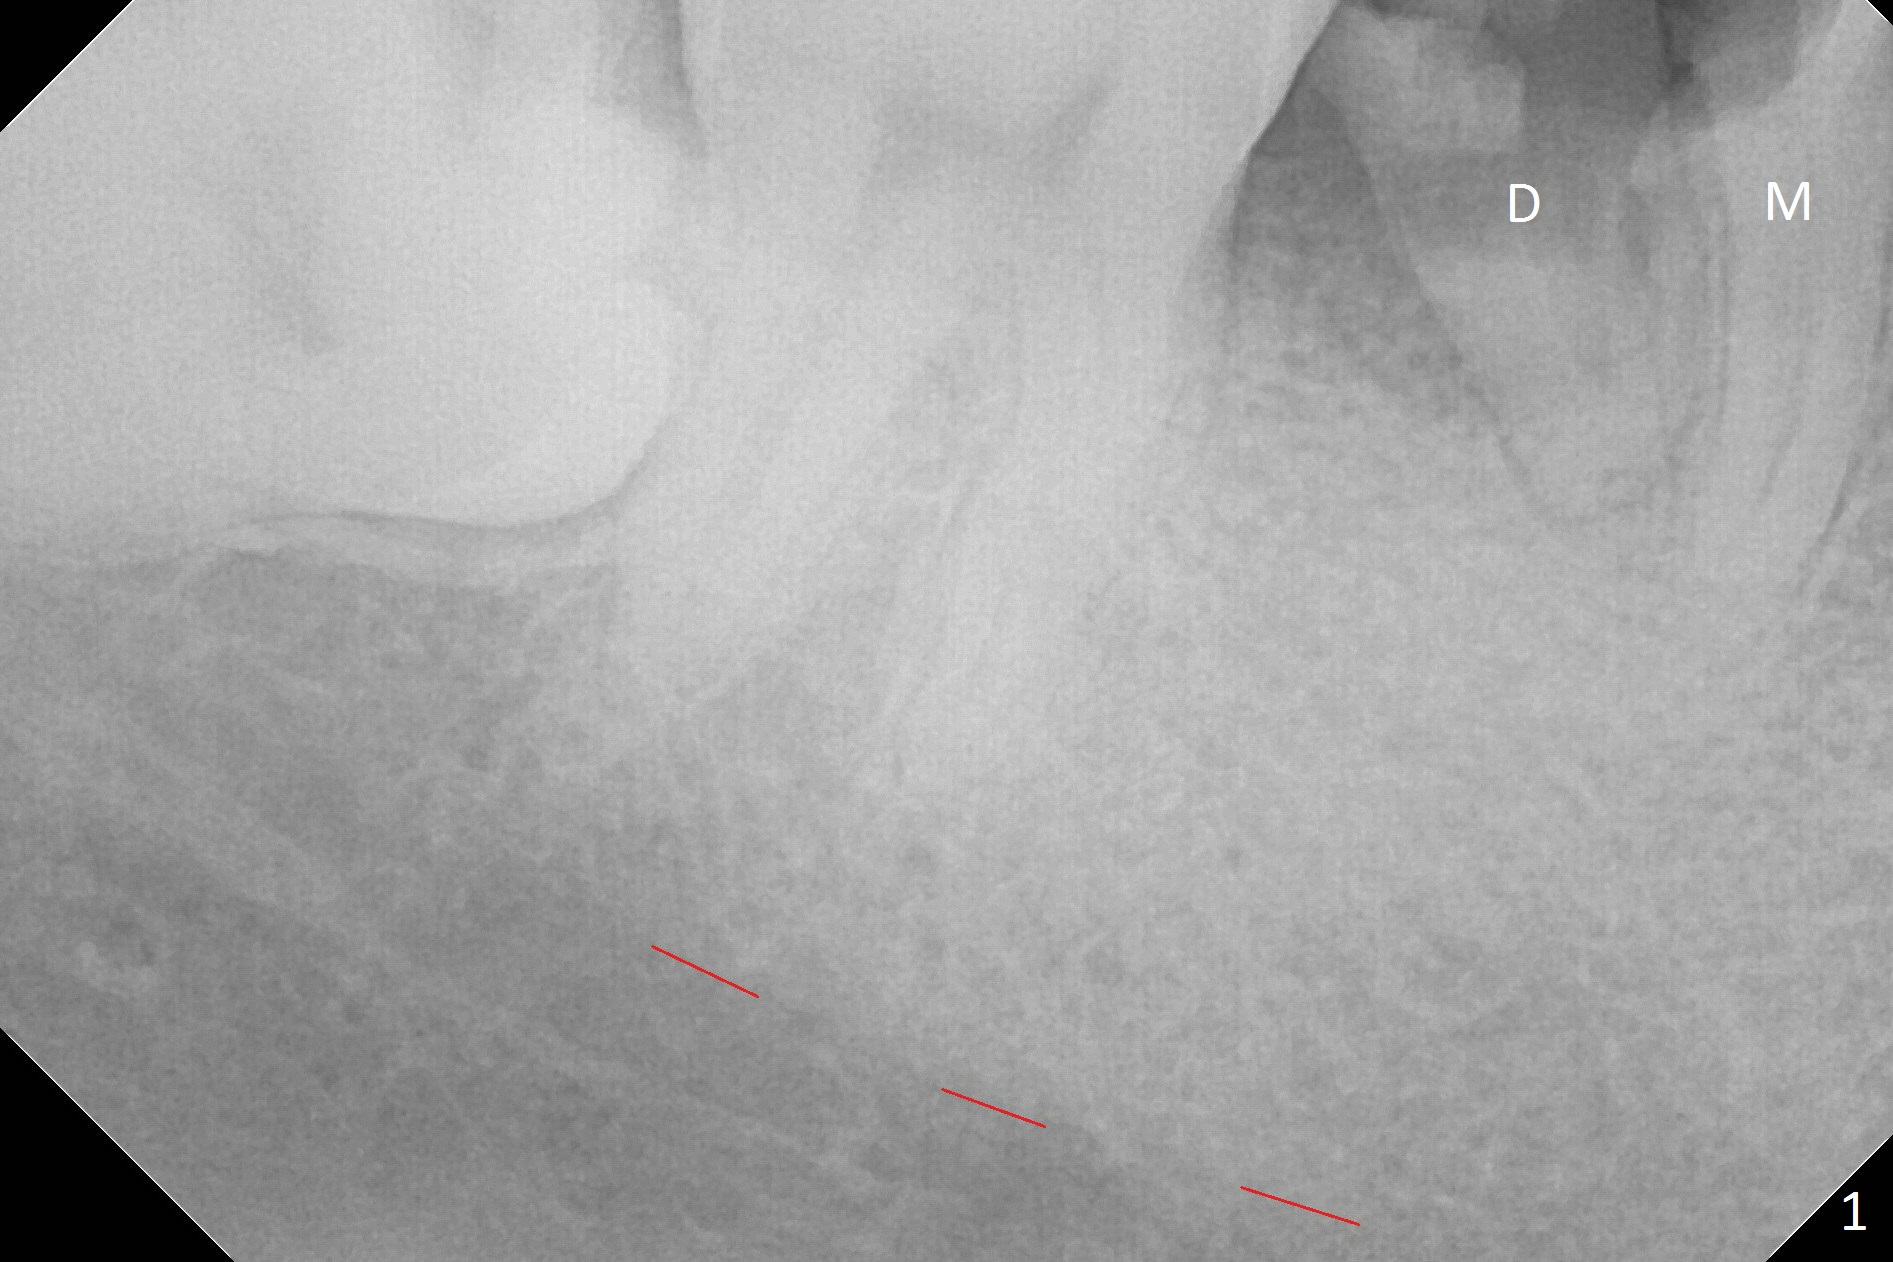

A 43-year-old man has residual roots at #30 (Fig.1). The mesial (M) and distal (D) roots approximates each other so close that the septum is thin (Fig.1,3-5). The latter is unfavorable for osteotomy. After extraction (Fig.5), the middle of the septum (Fig.8a (axial section of the sockets)) will be sectioned (Fig.6, 8b,c) prior to initial osteotomy (Fig.7,8d). The depth of the latter will be ~ 5 mm (Fig.2 red line) for a 13 mm (pink line) IBS implant.